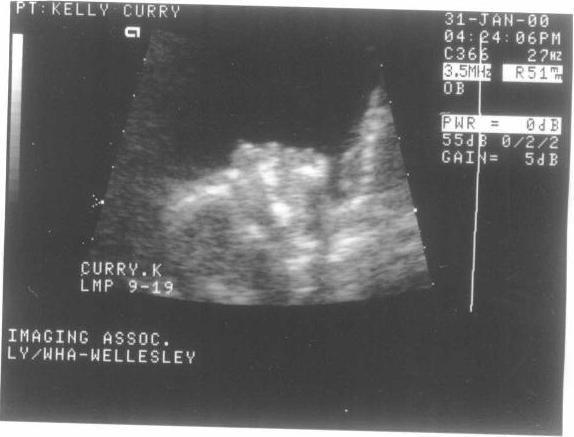

Deeder, age -5 months

updated pictures expected in July!